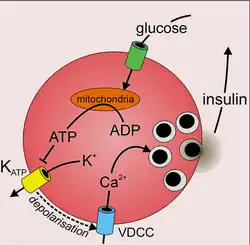

De belangrijkste factor die de afgifte van insuline vanuit de alvleesklier bepaalt, is de glucoseconcentratie, de bloedsuikerspiegel in het bloed. Andere stimulerende factoren zijn het gehalte van in het bloed aanwezige aminozuren, vetzuren en de werking van het parasympathische zenuwstelsel. Wanneer de bloedglucosespiegel stijgt, gaat glucose de bètacellen binnen via een membraaneiwit, de glucosetransporter GLUT-2. Glucose wordt in de bètacel via de normale weg, door middel van celademhaling omgezet. Hierbij spelen glycolyse en de citroenzuurcyclus een rol. Het leidt ertoe dat de concentratie ATP in de bètacel stijgt. Het gevormde ATP blokkeert kalium-ATP-kanalen, waardoor de celmembraan depolariseert en het spanningsafhankelijk calciumkanaal zich opent. De calciumconcentratie in de cel stijgt en dat leidt ertoe dat insuline wordt afgegeven. Consumptie van veel suiker, bijvoorbeeld door frisdrank, leidt tot de productie van insuline.

Bètacellen bereiken een nauwkeurige controle van de insulinesecretie door middel van uitgebreide cel-celcommunicatie met de andere celtypen in het eilandje van Langerhans, met name de glucagonproducerende alfacellen en de somatostatineproducerende deltacellen.[26] In bètacellen is de stijging van de bloedglucosespiegel (glycemie) na voedselinname direct gekoppeld aan insulineafgifte. Insulineafgifte is glucoseafhankelijk en wordt, naar analogie van de excitatie-contractiekoppeling in spieren, het stimulus-secretiekoppelingsmechanisme genoemd.